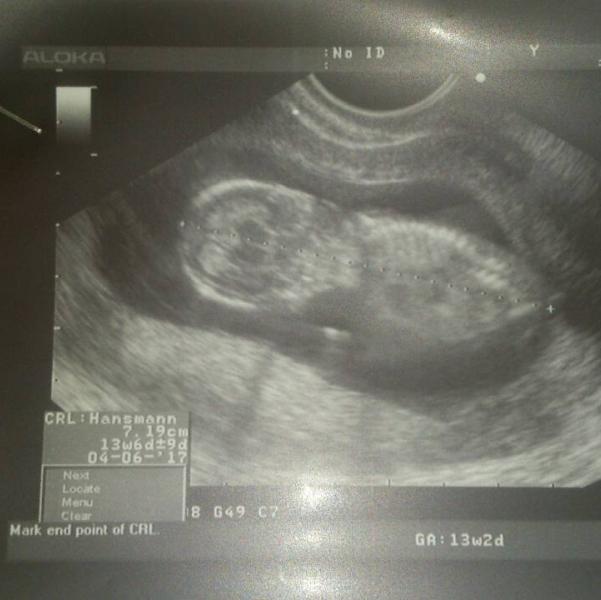

Сходили с мужем на узи, посмотрели нашего ребеночка после перенесенной мной ветрянки:( ручки, ножки, пальчики все есть:) немного помахал нам ножками и ручками:) Врач сказала, что скорее всего ждем мальчика:))) Отправляют нас в 19-20 недель в генетический центр на узи, там уже точно скажут про здоровье маленького, очень надеюсь, что все будет хорошо:-)